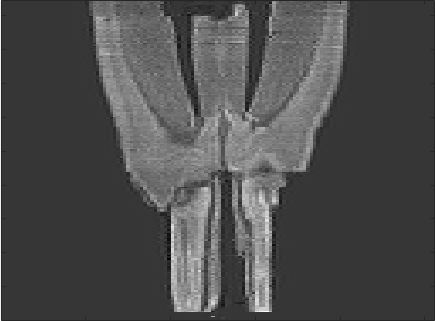

We present results for a histological serial sectioning of a sectioned mouse brain, data courtesy of Oliver Schmitt. For results on DCE-MRI data we refer to [2]. Fig. 1 shows results for a sequential linear pre-registration, the new based registration, and a standard sequential based registration as a reference (robust and fast to compute).

Although only one iteration was performed for the sequential registration, the computing time is about six times as for the approach. The result also shows a much stronger spatial correlation, indicating that the sequential approach has not yet converged.